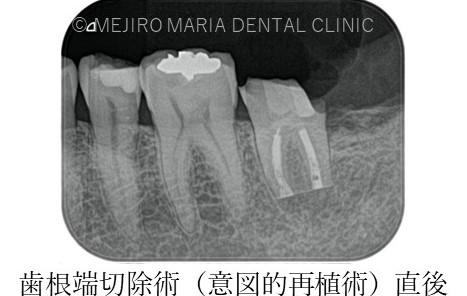

【症例】根管治療後も症状の改善が認められないケース・歯根端切除術(意図的再植術)を施し治癒へ

今回のような最後方臼歯(一番後ろの歯)に対しては、解剖学的に骨の厚みや器具の到達を考え、意図的再植術を適応させることになります。

治療後の様子

違和感や痛みは術後1ヶ月程で消失し、3ヶ月後には術直後に見られていた左下7番根尖部に確認できた透過像も消失し、順調に骨が作られていることが確認できます。